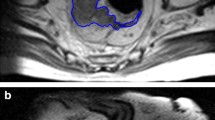

Fifty-five female patients aged 25 to 75 years (mean age = 50.4 ± 12.2 years) were enrolled in the study which included 49 patients with a single breast tumor and 6 patients with multiple tumors. All patients were diagnosed with invasive ductal carcinoma by pre-NAC puncture biopsy and received NAC prior to surgical resection. Clinical and pathological data of the study were listed in Table 1. The pCR rate was 30.9% (17/55) (mean age = 50.7 ± 9.4 years), whereas non-pCR rate was 69.1% (38/55) (mean age = 49.5 ± 10.4 years). The median maximum diameters of the lesions were 2.6 cm (range: 2.3–3.7 cm) and 4.2 cm (range 3.1–5.4 cm) in the pCR and the non-pCR group, respectively; and the mean diameters were 2.9 ± 1.1 cm and 4.3 ± 1.9 cm, respectively. Except for the maximum diameter (p = 0.002), there were no statistically significant differences between pCR and non-pCR groups of patients. Figure 3 demonstrates the segmentation of breast lesions on CE-MRI.